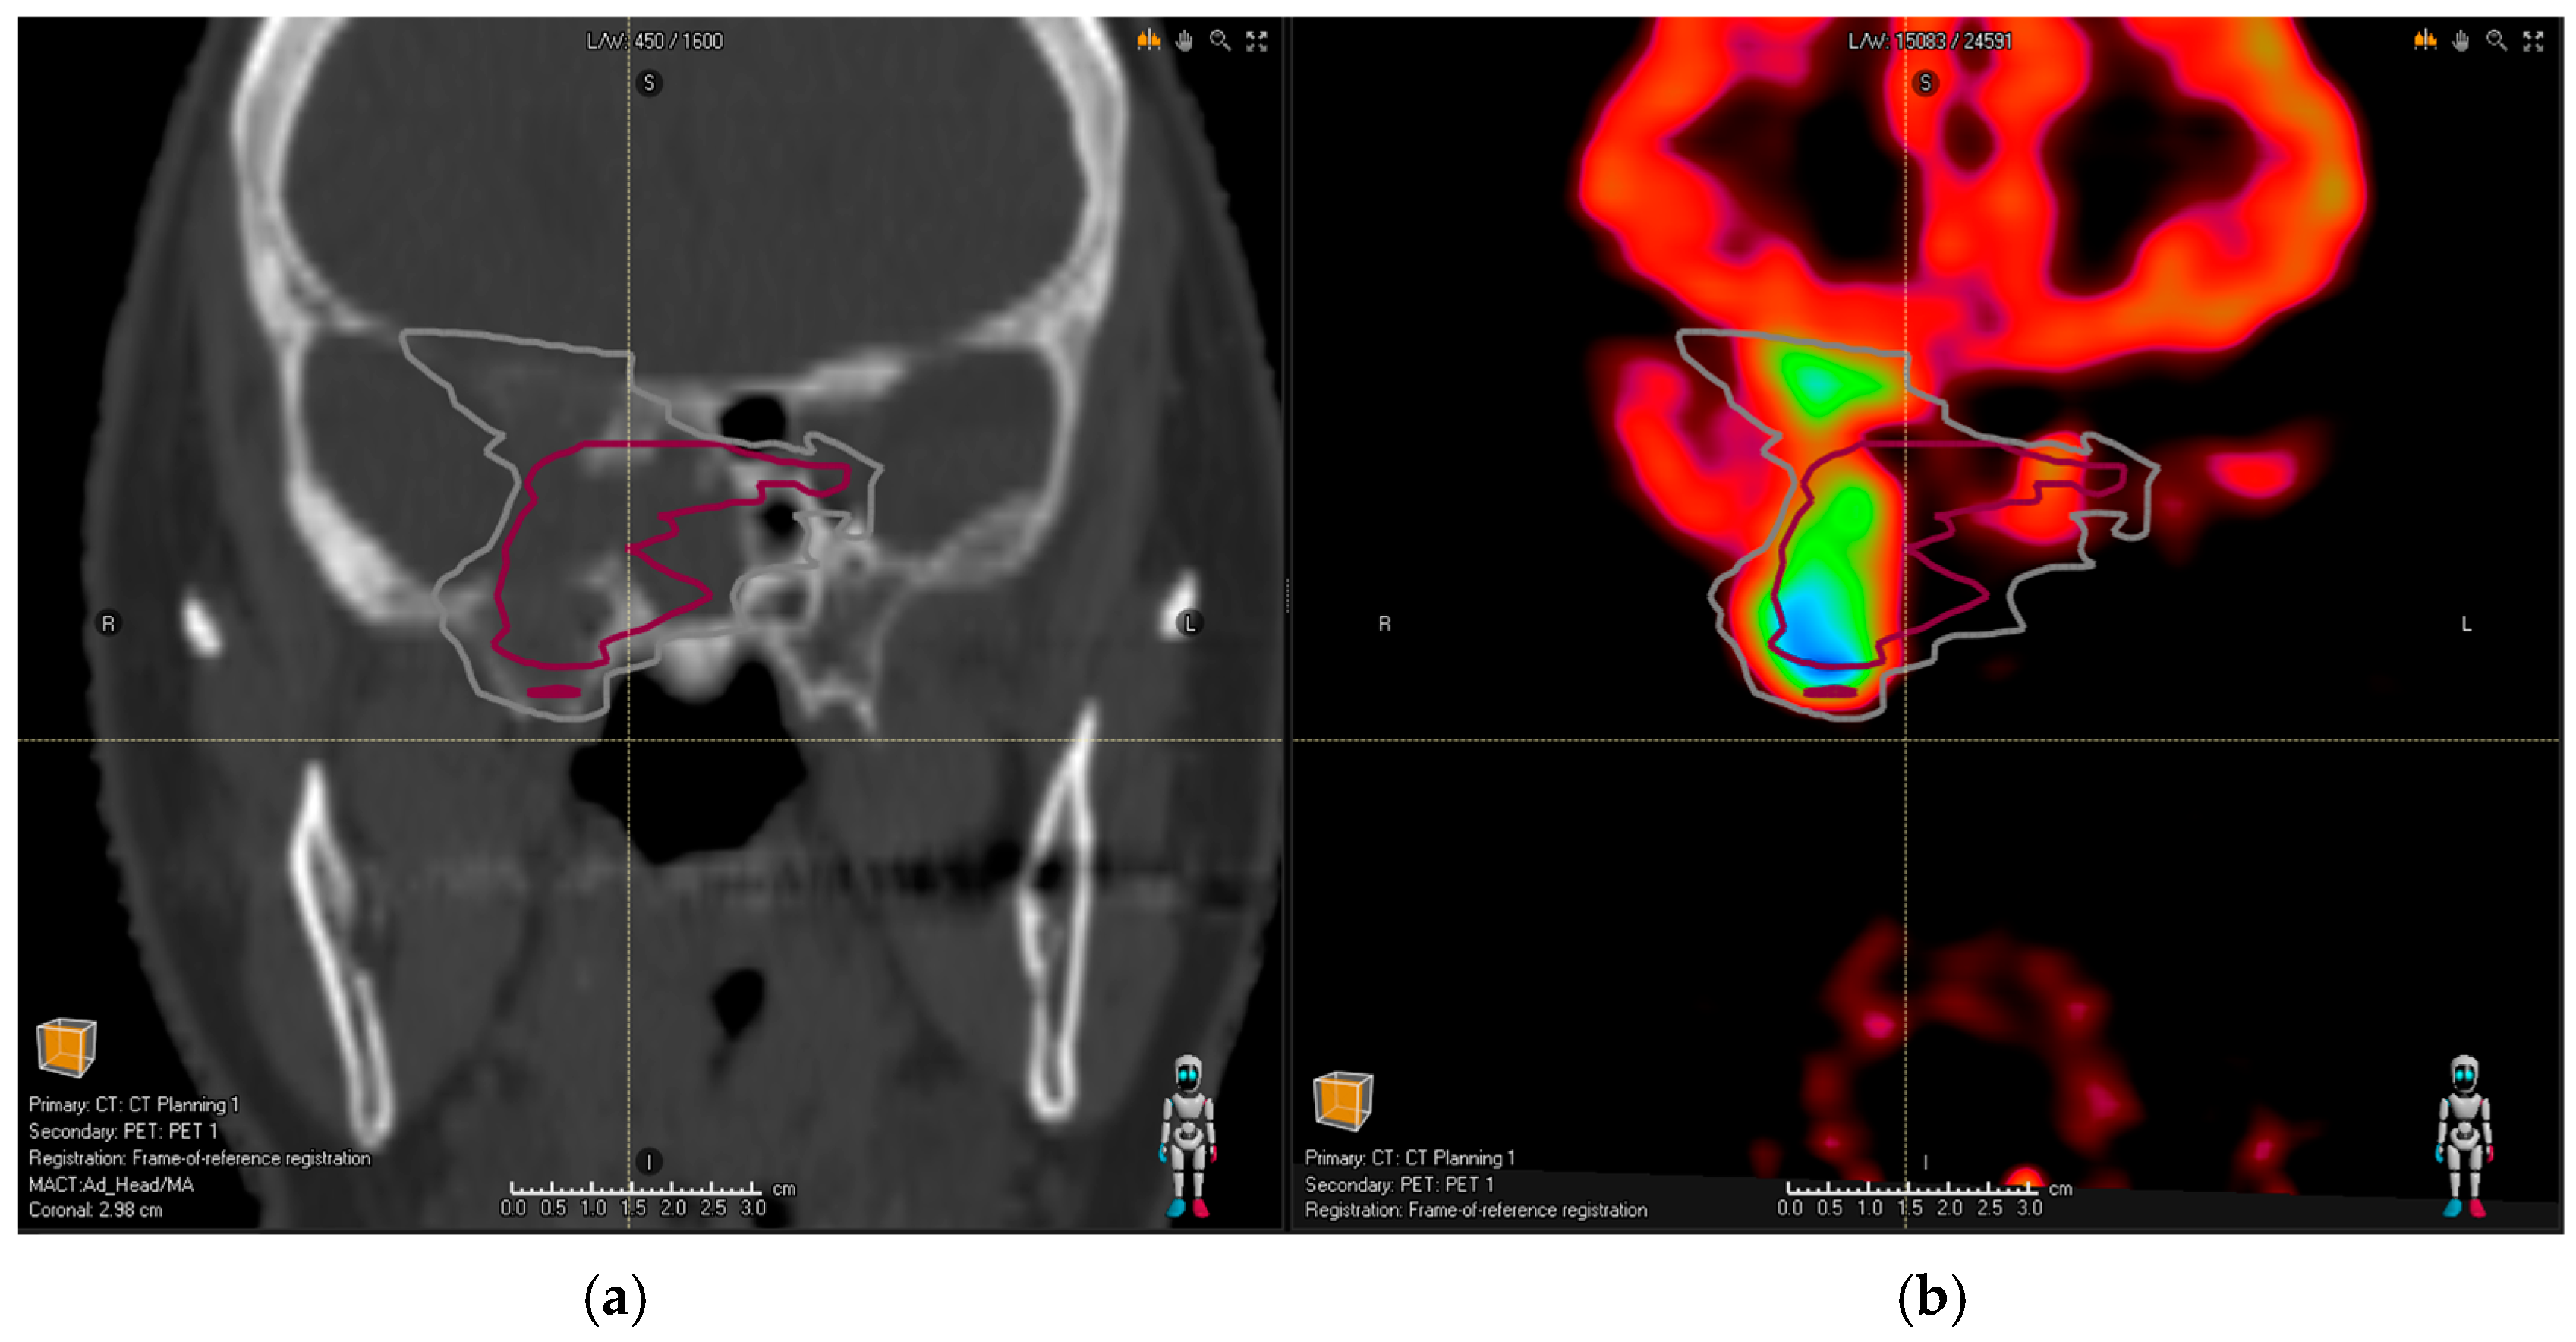

• Extensive bone infiltration in the frontobasis area from a case of an aggressive PitNET (as depicted in Figure 2).

Figure 2. Planning CT image (a) of a patient with an aggressive pituitary adenoma. Red contour shows the common MRI volume of all observers; (b) the addition of PET/CT revealed further bone infiltration into frontobasis (difficult to identify based on structural imaging alone as the patient had co-existing osteoporosis)—the gray contour representing common PET/CT and MRI volume takes this finding into account.

In all these cases, the new tumor volume first identified with the aid of DOTA PET/CT should be considered relevant for the proton treatment plan. There was no relevant tumor volume missed by observers in MRI compared to PET/CT for glomus tumors. Figure 1a shows the planning CT image of a patient with pituitary adenoma; Figure 2a shows the planning CT image of a patient with an aggressive pituitary adenoma.